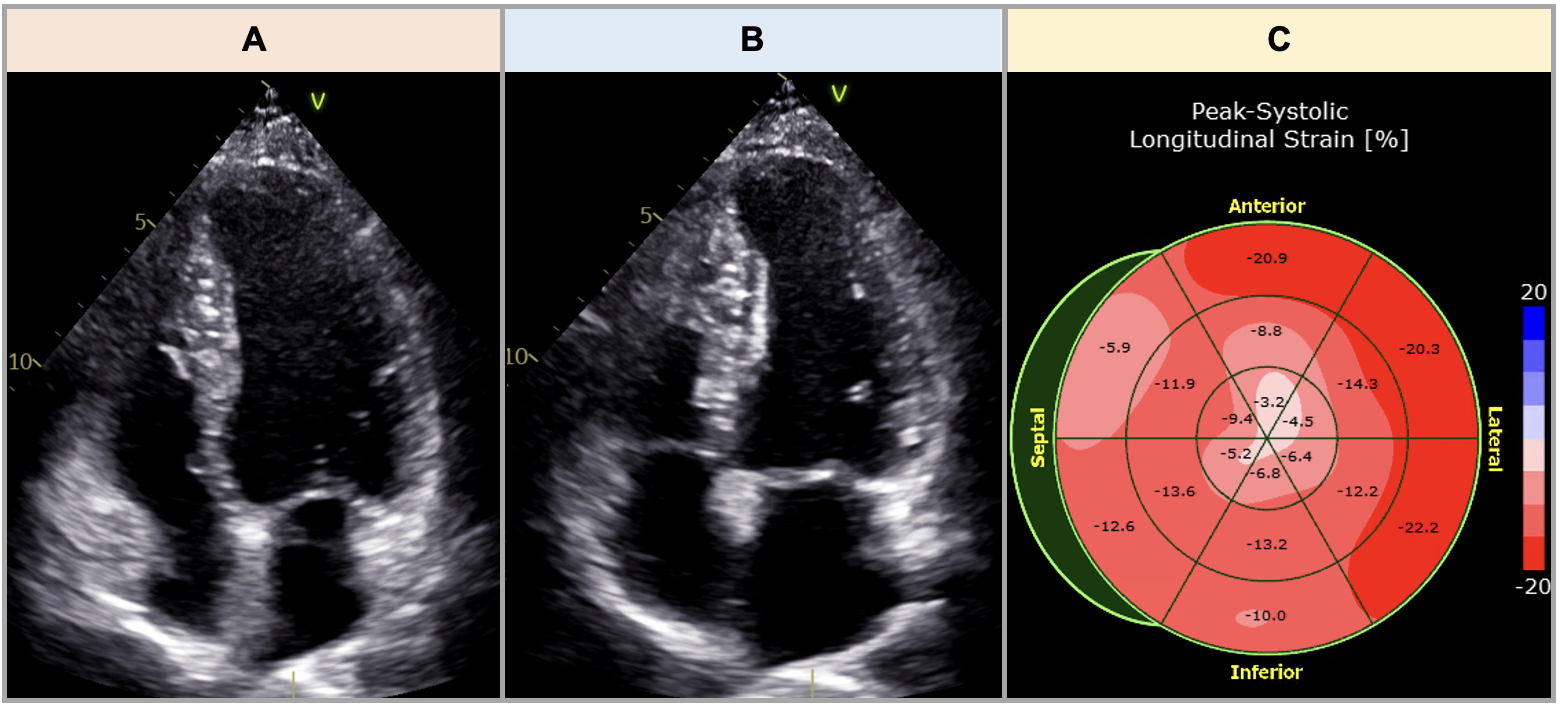

She underwent planned cesarean delivery at week 37 of gestation. The following day, coronary computed tomography angiography (CCTA) revealed severe stenosis of the mid-left anterior descending (LAD) artery (Figure 2A). Hours later, she had recurrence of chest pain without EKG changes, and HS-troponin increased to 7,000 ng/L. The decision was made to proceed with invasive coronary angiography, which confirmed SCAD in the mid-LAD (Figure 2B). Revascularization was not pursued given her hemodynamic stability, and she was managed conservatively.

In PSCAD patients, invasive angiography has been associated with an increased risk of iatrogenic dissections and may pose risks to the fetus, limiting utility. Non-invasive imaging such as CCTA may be considered in clinically stable patients; but there is limited data evaluating the diagnostic accuracy of CCTA in SCAD.